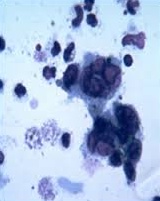

Tzanck smear = multinucleated giant cells

reacting T knight with 8's: Reactive cytotoxic CD8+ T cells (Downey, or atypical cells) lymphocytosis, seen on blood smear (stain on cloth)

"Owl O cereal = Owl's eye inclusions seen in CMV"

tank: Tzanck smear = multinucleated giant cells